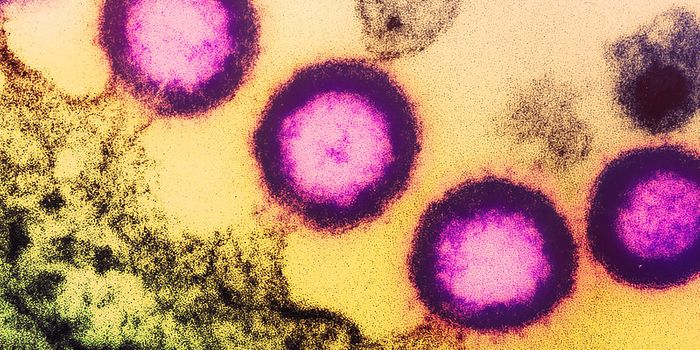

AUG 27, 2024MicrobiologySince the start of the COVID-19 pandemic, the virus that causes the illness - SARS-CoV-2 - has had a practically infinit ...

SEP 08, 2024MicrobiologySARS-CoV-2, the pandemic virus that causes COVID-19, has mutated endlessly since it burst on the scene in late 2019. An ...